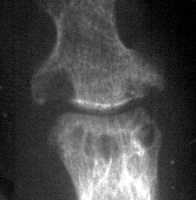

arthritis (RA) is a disease of the synovium. The hallmarks of rheumatoid

arthritis are symmetrical joint involvement, marginal erosions, uniform joint

space narrowing, juxta-articular osteoporosis, and soft tissue swelling. There

is a lack of hypertrophic changes. However, secondary osteoarthritis may lead

to productive changes.

2. Erosion pattern:

Early erosive changes are seen involving the "bare areas" of

metatarsal heads. In late stages of RA, subluxations may occur at the MTP

joints with the proximal phalanges subluxating in fibular direction and metatarsal

heads subluxating in plantar direction. Tarsal bones are involved as a unit

with uniform joint space loss. Bony ankylosis of tarsal bones may occur. In

addition, erosions of the calcaneus may occur at the attachment of the plantar

aponeurosis and/or attachment of Achilles tendon.

3. Differential diagnosis:

The absence

of bone proliferation and bony ankylosis, and the presence of osteoporosis are

common finding of rheumatoid arthritis and are useful in the differentiation

of rheumatoid arthritis from seronegative arthritis.